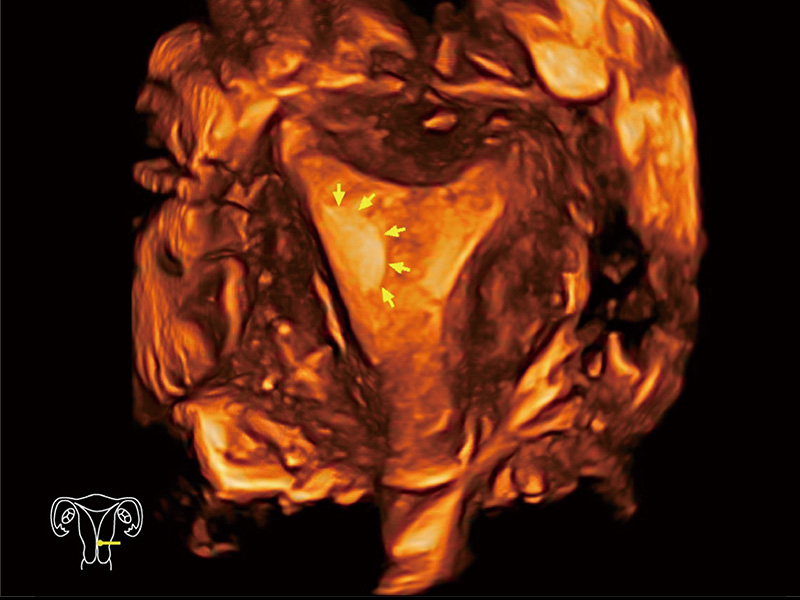

“生育问题”即关系民族复兴,也关系亿万家庭的幸福。随着婚育年龄推迟、社会压力增加等因素,越来越多人群也面临着“生不出、生不好”的问题。辅助生殖作为治疗不孕不育最有效的方法之一,也逐渐成为育儿新希望。而超声检查能为生殖需求人群的初诊评估提供宝贵的信息。 P20 Elite是玖鼎集团匠心打造的一款生殖应用型彩超。她继承玖鼎集团高端极光平台,突破性地将多款新型芯片及硬件模块进行整合,均衡了高端系统性能与小巧灵动机身。P20 Elite卓越的图像质量搭载专科探头,旨在为您提供全面的辅助生殖解决方案。

P20 Elite配备了丰富的生殖探头群和临床应用功能,在卵泡监测、穿刺取卵、胚胎移植、妊娠确认等领域,为生殖需求人群提供了新的临床机会,重新定义高端超声如何应用于生殖健康检查。